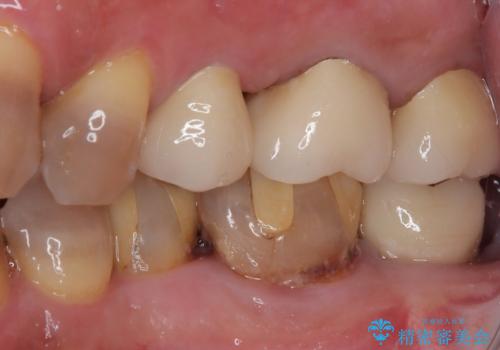

- 左下奥歯のインプラント治療と左上の被せもののやり替えを希望されて来院された患者様です。

左上の奥2本は他院で根管治療と仮歯まで入れている状態です。根管治療のやり替えは希望されなかったため被せものから治療していくことにしました。

その手前の小臼歯は根尖病変が認められるため根管治療のやり直しからしていくこととしました。